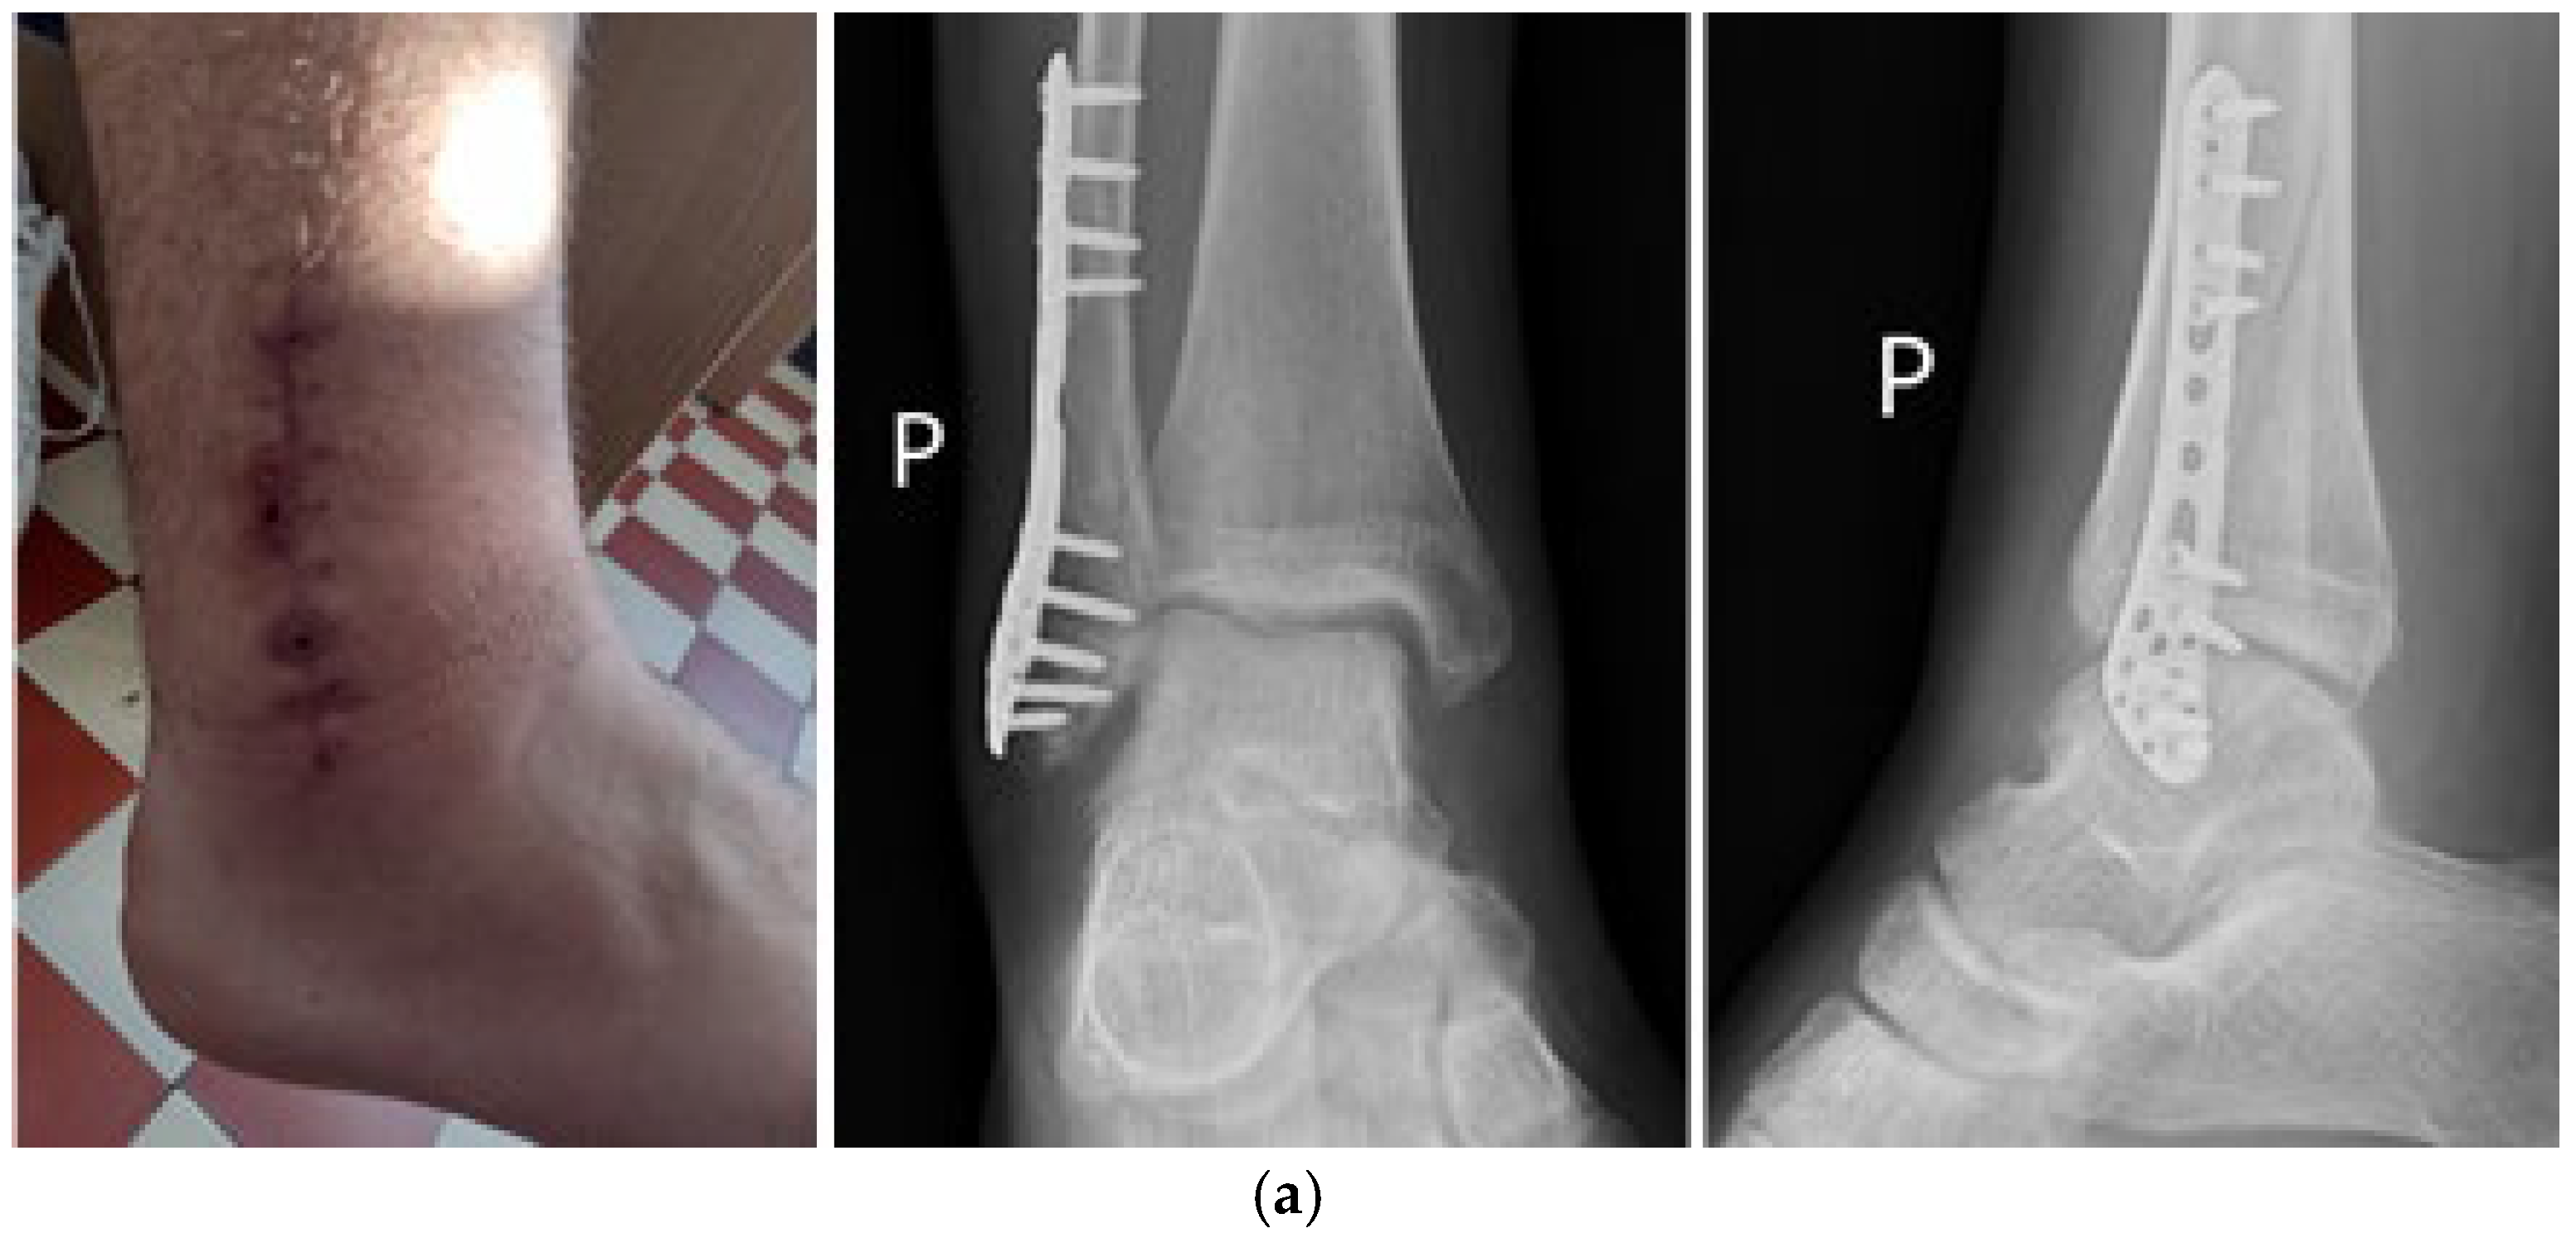

7. Macroscopic Observations of Interacted Surfaces of Removed Implants—Author Observations